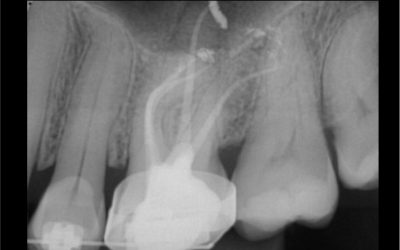

Bassi Logicによる臨床例

6500の文書がすでに切り替えられており、結果が出ています。毎日の手順からの臨床例は私たちがファ

イルを改善するのを助けるだけでなく、Endosが学ぶためのリソースも提供します。